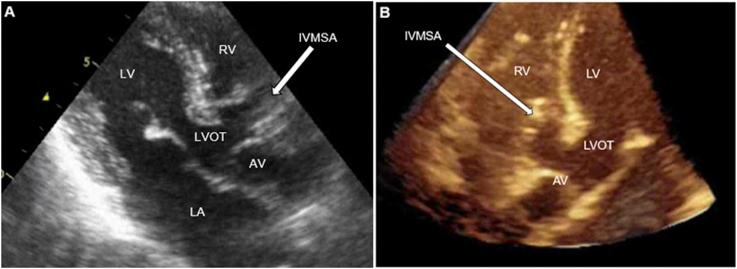

Multimodal Imaging Characterization of a Congenital Multilobular Interventricular Membranous Septal Aneurysm in a Patient Presenting with Embolic Stroke.

• TTE is often performed to search for cardiac sources of emboli. • TTE must be comprehensive and assess the atria, valves, and ventricles. • TTE can be utilized to identify IVMSA as a rare cause of recurrent strokes. • Comprehensive imaging studies should be utilized to confirm the diagnosis of IVMSA. • Multidisciplinary care is necessary in the management of these patients.